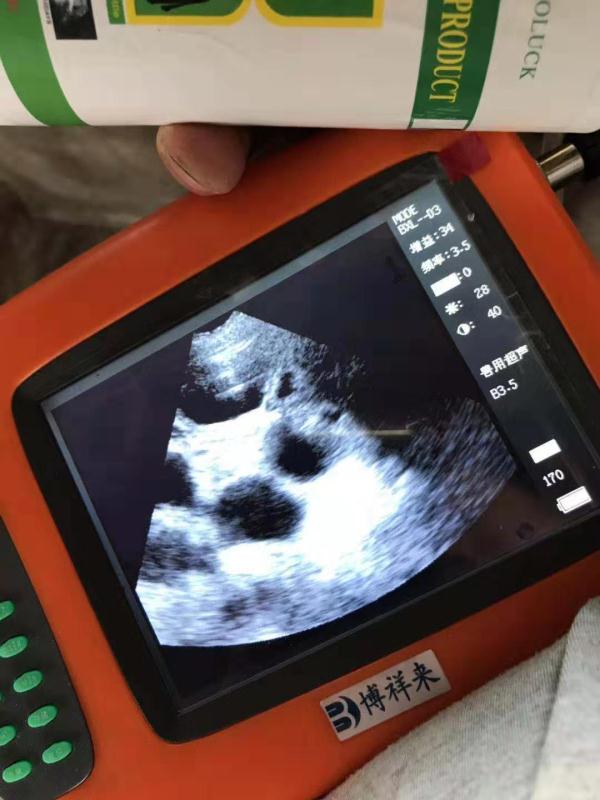

4. 观察B超图像:当B超仪器工作时,会产生一系列的图像,这些图像可以帮助确认母猪的怀孕情况。医生或技师会观察这些图像,并注意任何异常。

通过以上步骤,养殖人员可以判断母猪是否已经怀孕。一般来说,怀孕母猪的子宫内部会出现黑色的斑点或条纹。这些斑点或条纹是由于胎儿的存在造成的,它们会反射出B超探头发出的声波,并在屏幕上呈现出来。

母猪怀孕后的超声图像上可以看到多个黑洞,而空怀母羊则只能看到一条亮白色的细线